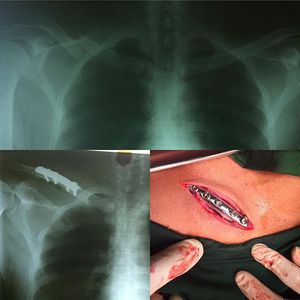

Clavicle fixation

And...another clavicle fixation